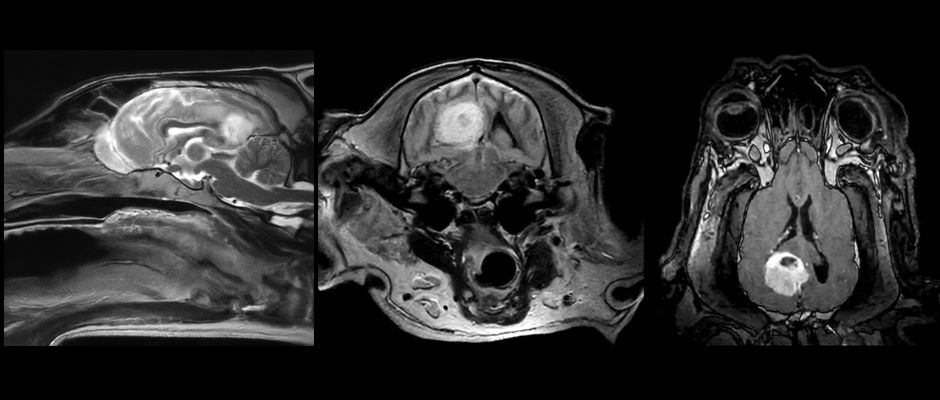

The O-scan Vet has significantly improved our diagnostic efficiency. It’s particularly valuable for brain cases and for cases where intramedullary lesions are suspected, where MRI findings guide treatment decisions.

For head imaging, size has almost never been a limitation. For spinal imaging, however, the system is suitable mainly for patients under approximately 10 kg.

How would you rate the image quality provided by this compact MRI system?

The image quality is clearly superior to what we initially expected from a low-field MRI. It provides reliable and detailed images that allow confident diagnosis in most intracranial and spinal cases.

We’re looking forward to the new features planned for 2026, including DWI and thinner FSE sequences, which will significantly enhance diagnostic capabilities for brain disorders and imaging of very small animals.